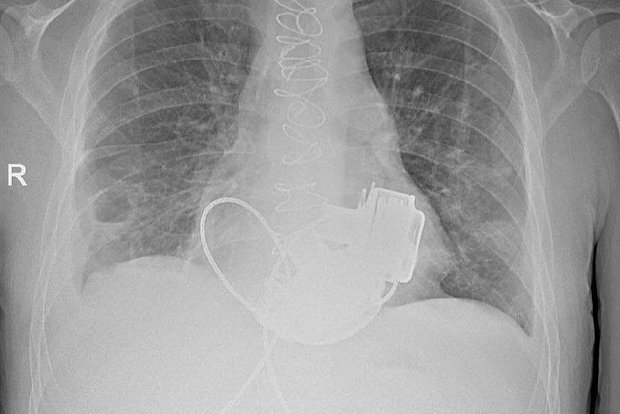

Уникального пациента без пульса выпишут из российской больницы

Комздрав СПб: Из Мариинской больницы выпишут уникального пациента без пульса

Фото: Комздрав СПб / Telegram